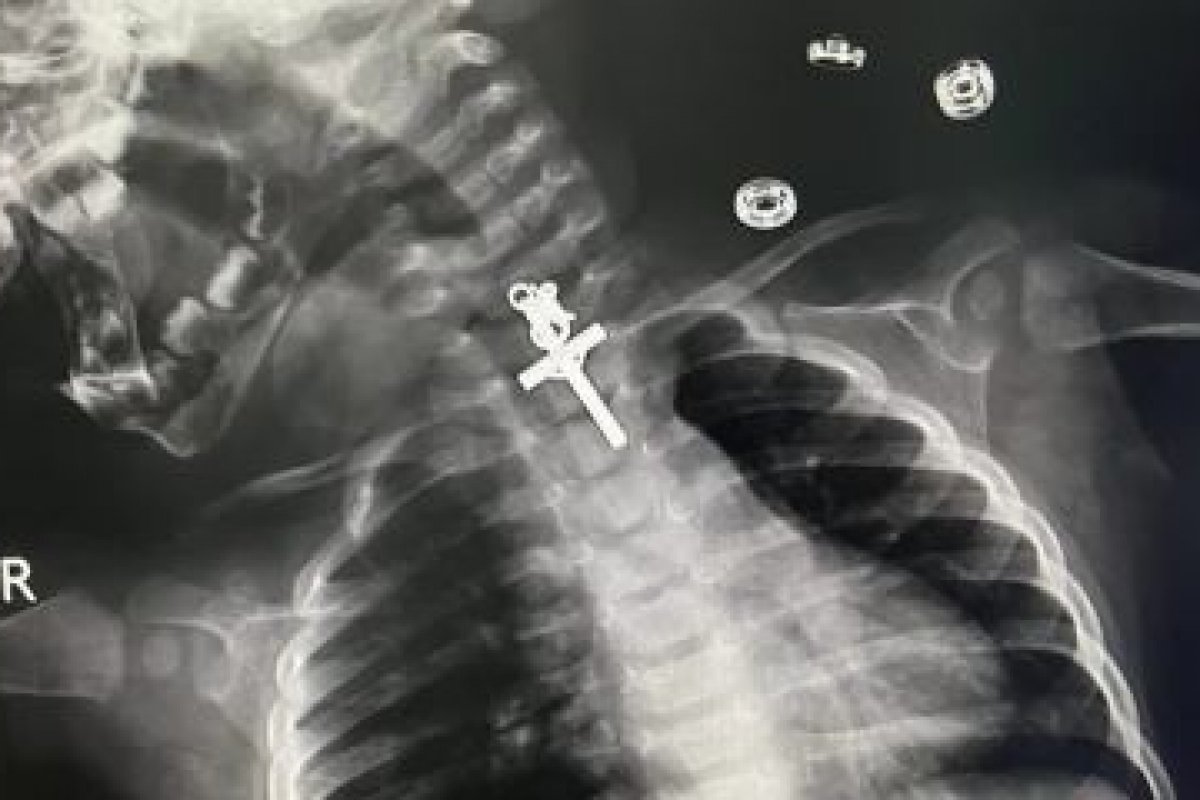

Um bebê de 10 meses ficou com um crucifixo preso dentro de garganta em La Libertad, no Peru. Imagens de raio-x mostram o objeto alojado no esôfago.